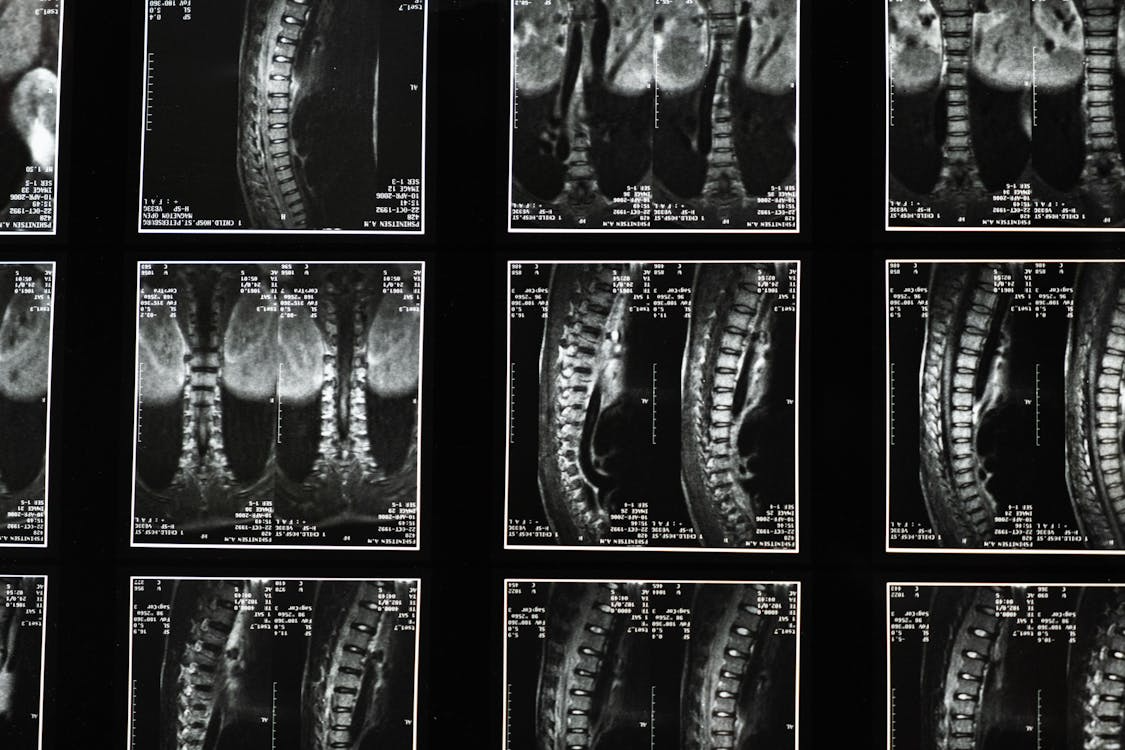

An X-ray of a back.